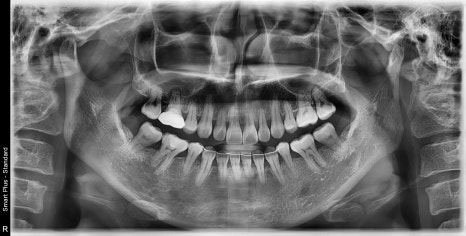

| 발치 전 | 발치 후 |